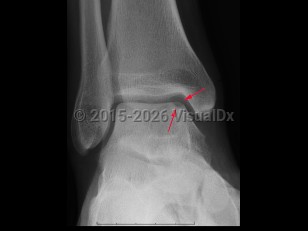

Imaging Studies image of Osteochondral defect - imageId=7921453. Click to open in gallery.  caption: '<span>Lucency at the medial talar dome compatible with an osteochondral defect.</span>'

Lucency at the medial talar dome compatible with an osteochondral defect.